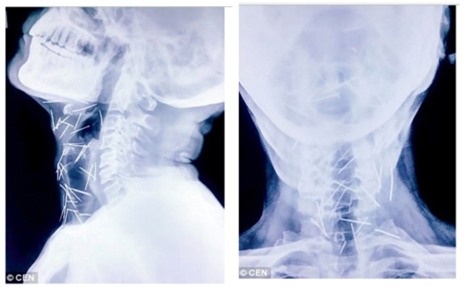

Daily Mail đưa tin, ông Badrilal Meena (56 tuổi) đến từ TP Kota, bang Rajasthan, miền Bắc Ấn Độ được đưa vào bệnh viện để phẫu thuật ngón chân cái thì bác sĩ phát hiện trong chân ông có nhiều cây kim. Sau khi tiếp tục kiểm tra, các bác sĩ phát hiện có tới 75 cây kim trong cơ thể ông Meena. Trong số 75 cây kim, có 40 cây nằm trong cổ họng, 25 cây ở chân và 2 cây ở cánh tay.

Ảnh chụp X-quang cho thấy kim nằm trong cổ bệnh nhân. Ảnh: DAILY MAIL |